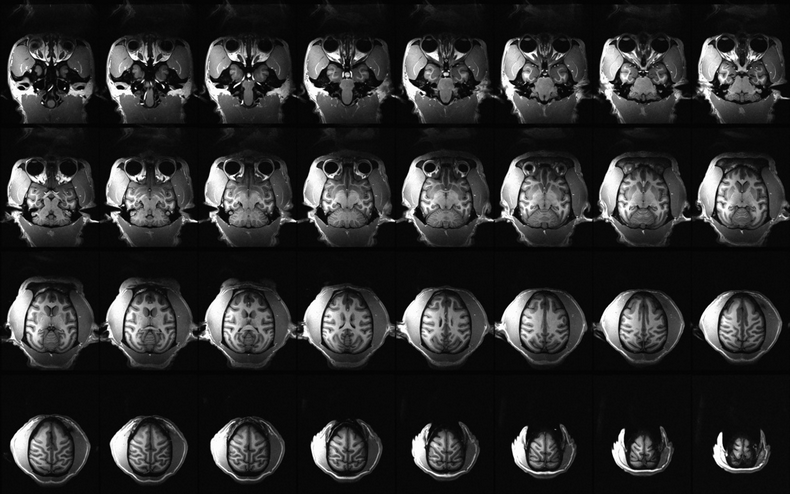

- 关键词:猕猴,磁共振,全脑, T2加权,EPI图像

预定本数据集为收集到的2020到2024年中国科学院生物物理研究所刘宁团队对8只健康成年猕猴脑部核磁共振扫描数据,共扫描17次,主要扫描序列包括T2w、fMRI等。通过该数据可进一步了解健康猕猴脑部结构和功能与人类的同源性,为比较灵长类动物与人类大脑在解剖结构、神经网络连接及功能活动等方面的异同提供重要参考,有助于推进脑科学基础研究和人类脑疾病模型的建立。

扫描仪类型:西门子Prisma 3.0T磁共振扫描仪

线圈:8通道猴线圈/4通道动物线圈

团队使用西门子Prisma 3.0T磁共振扫描仪磁共振扫描仪对实验猴脑部进行核磁扫描,该核磁设备质量符合国家相关标准,所有设备操作者均接受上岗培训, 以确保获得合格的高清晰度图像。